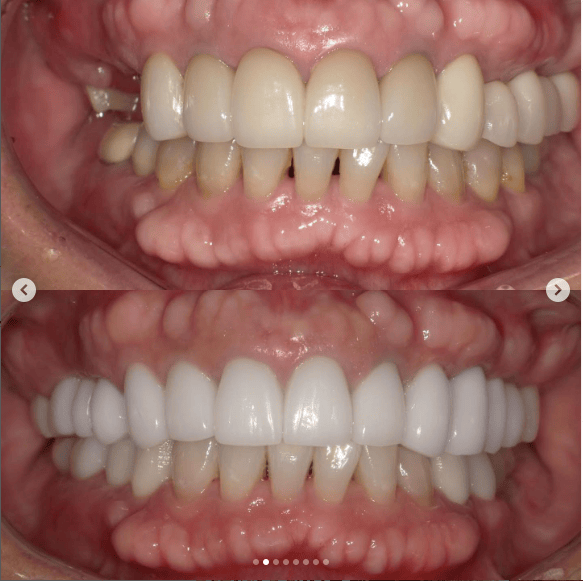

口腔内を全体的に治療させて頂いた患者様の症例です。

もともと透明感の無い大きなセラミックが入っていた前歯に、透明感がありスマートな形のセラミックを入れました。また、歯茎のラインにも違和感があったため、今回の治療で治しています。

セラミックと歯茎の境目が綺麗になるかどうかは歯科医の腕次第ですが、とても綺麗にできたと思います。

また、インプラントなどで奥歯の噛み合わせも治療いたしました。

前歯の審美性にご満足いただき、以前より食事がしやすくなったとお褒めの言葉を頂きました。

当院では噛み合わせなどの機能面や審美性を考えた上での全体的な治療が可能です。